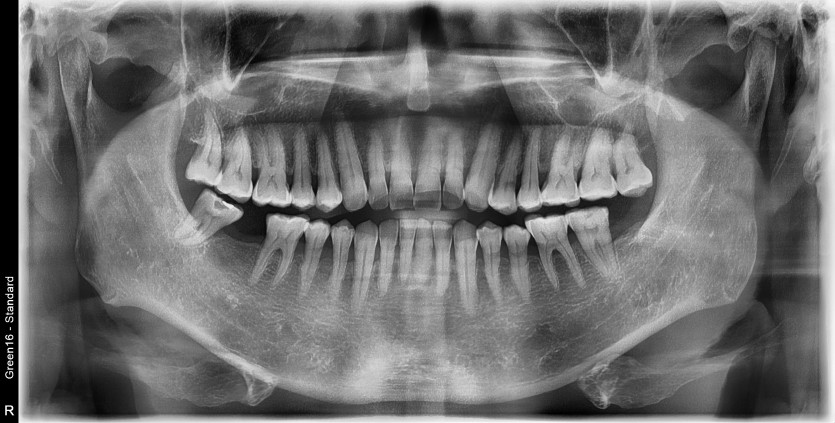

#18.48 사랑니 발치

구강 외과 전문의가 당일 발치했습니다.